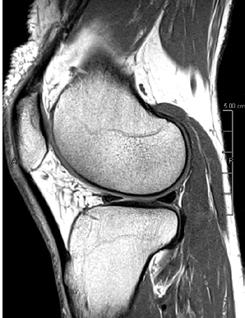

PD STIR - 1024 x 1024 matrix - 3mm slice thickness

Sag T2 - 0.5 x 0.5 min - 0:56 min Ax PD FatSat - 0.6 x 0.6 mm - 1:30 min Cor PD FatSat - 0.6 x 0.6 mm - 1:15 min Cor PD - 0.5 x 0.5 mm - 0:58 min © 2020 CANON MEDICAL SYSTEMS // MREU200040

Fast knee protocol with AiCE on Vantage Orian 1.5T